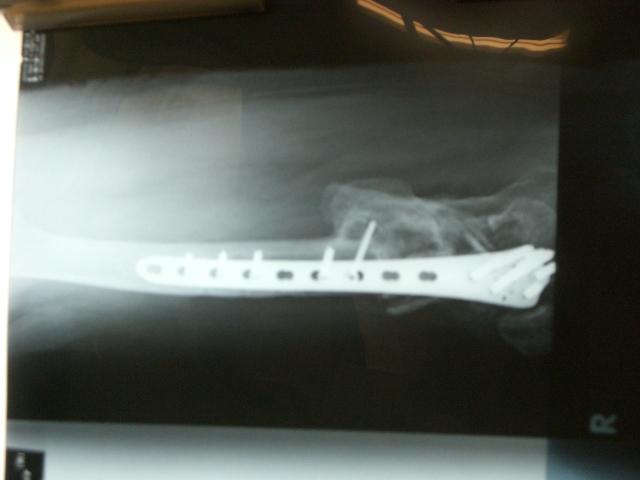

6/22¤Ë·è¹Ô¤¹¤ë»ö¤òDr¤ÈÂǹ礻¤·¤Æ¤­¤Þ¤·¤¿¡£

100415¤Î¹ü (1)¤Þ¤À¼ê½Ñ¤ÎÆâÍÆ¤ÇǺ¤ó¤Ç¤¤¤ë¤Î¤Ç¤¹¤¬

¤Þ¤º¡¢±¦É¨¤ò¶Ê¤²¤ë°Ù¤Ë

¶ÚÆù¤Ê¤É¤ÎÌþÃå¤òÇí¤¬¤¹¼ê½Ñ¤ò¤ä¤í¤¦¤È

·×²è¤·¤Æ¤¤¤Þ¤¹¡£

¥×¥ì¡¼¥È¤ò³°¤¹¤Î¤òÀè¤Ë¤·¤¿¤«¤Ã¤¿¤Î¤Ç¤¹¤¬

¿§¡¹¤ÈÊÀ³²¤â¤¢¤ë¤Î¤Ç¡¢¶Ê¤²¤ë¼ê½Ñ¤òÀè¹Ô¤·¤Æ¤ä¤ë»ö¤Ë¤·¤Þ¤·¤¿¡£

¥ê¥Ï¥Ó¥ê¤Ê¤É¤ò´Þ¤á¤Æ¡¢Ìó2¥ö·îÄø¤ÎÆþ±¡Í½Äê¤Ë¤Ê¤ê¤½¤¦¤Ç¤¹¡£